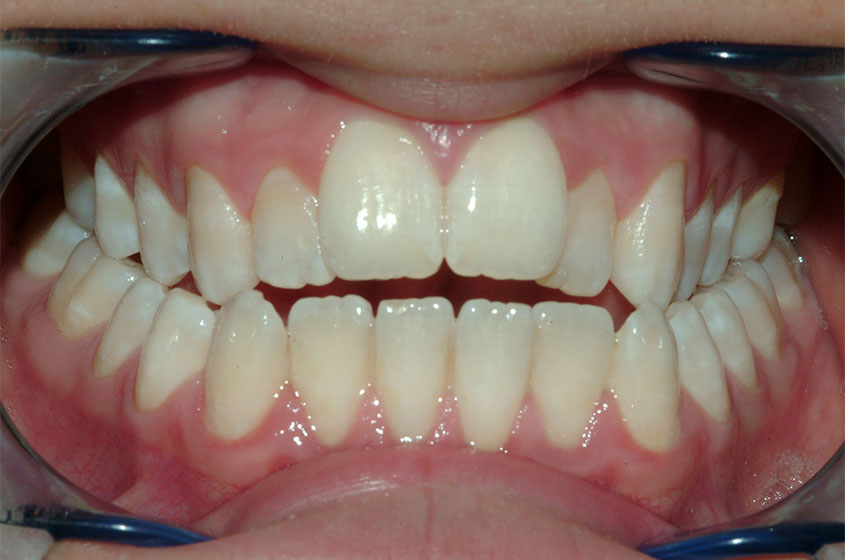

Buona occlusione

Questa è una buona occlusione! In una occlusione ottimale, ogni dente occlude con l’antagonista e con il dente adiacent...